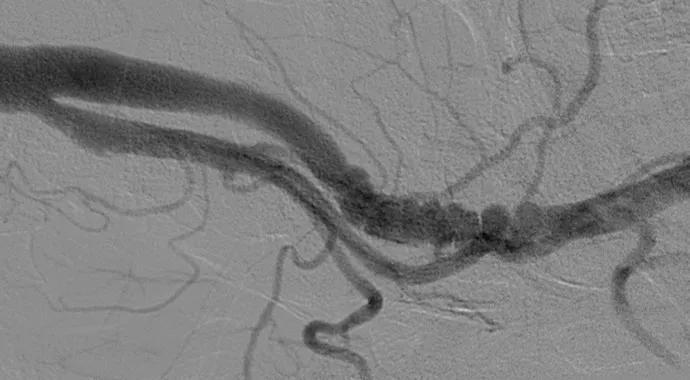

inset1

Angiograms showing bilateral multifocal FMD of the internal carotid arteries (“string of beads”).